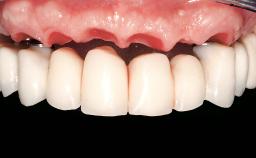

Immediate Loading of Six Implants in the Mandible and Six Implants in the Maxilla and Final Restoration with Full-Arch CAD/CAM Metal Framework FDPs Involving Digital Planning and Guided Surgery

Abutment Type CAD/CAM

Prosthesis Type FDP

Loading Protocol Immediate

Retention Screw-retained, with 4 or more splinted implants Screw-retained, with 4 or more splinted implants